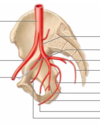

Qu’est qu’une artere?

Transportent le sang du cœur aux organes et aux tissus